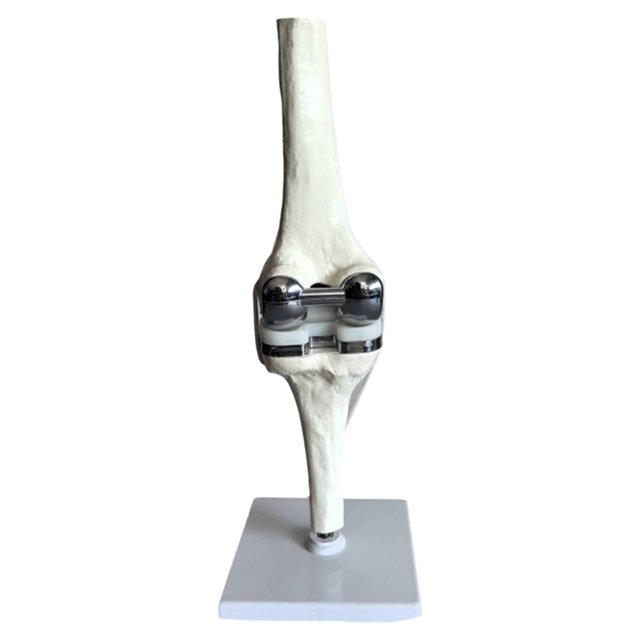

Knee Joint Replacement Devices

Knee Joint Replacement Devices When To Replace A Knee Joint What is knee replacement surgery? Learn about alternatives to joint replacement surgery to relieve your knee pain, plus how to know when you need to consider. A knee replacement is surgery to replace all or some of your knee joint. A knee replacement is an operation to replace damaged parts of the knee joint. During a total knee replacement (tkr),. When To Replace A Knee Joint.

Knee Joint Replacement Devices When To Replace A Knee Joint The whole knee is replaced. During a total knee replacement (tkr), the bone and cartilage at the end of the thigh bone and shinbone are removed. It’s a type of procedure called an arthroplasty (joint replacement). Most total knee replacement operations involve replacing the joint surface at the end of your thigh bone (femur) and the joint surface at the. When To Replace A Knee Joint.